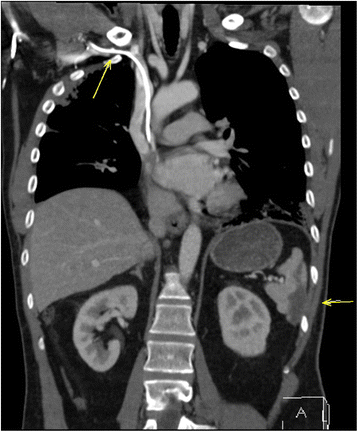

image